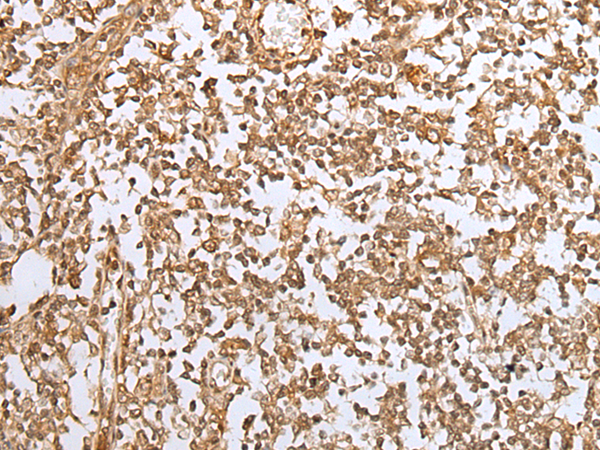

IHC positive control: |

Human gastric cancer and human tonsil |